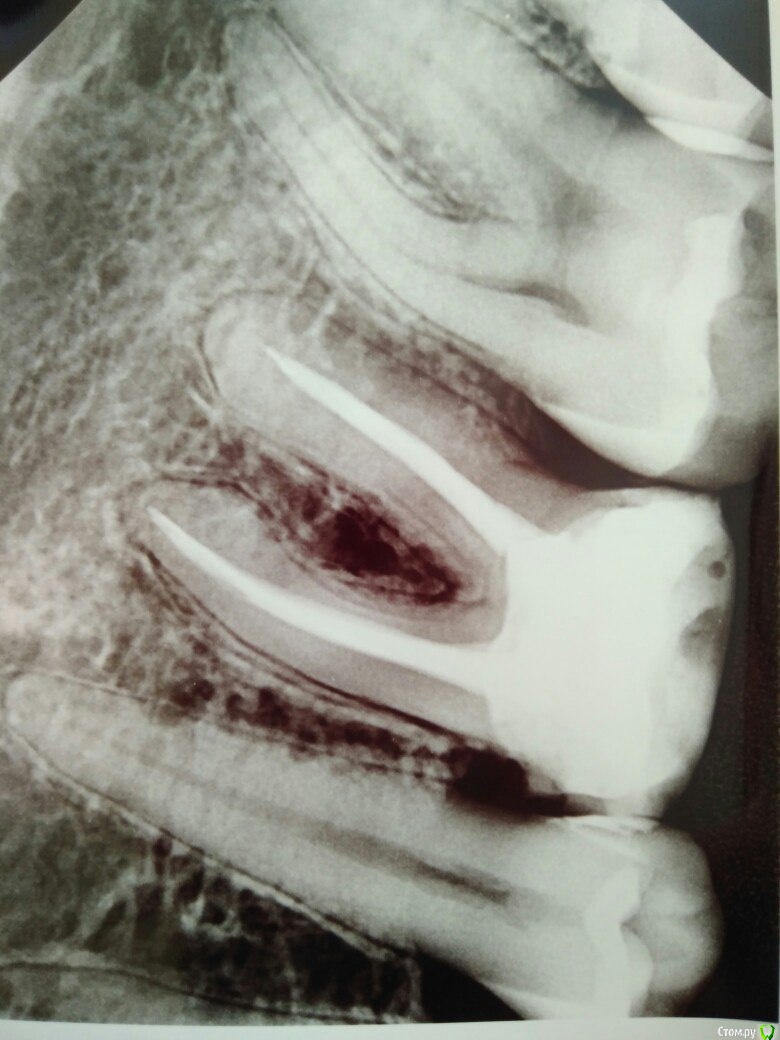

Аннана Опубликовано 28 февраля, 2018 Поделиться Опубликовано 28 февраля, 2018 Ставить коронку со штифтом, или оставить, пока сам не разрушится? Ссылка на комментарий

red_butler Опубликовано 28 февраля, 2018 Поделиться Опубликовано 28 февраля, 2018 Коронку 1 Ссылка на комментарий